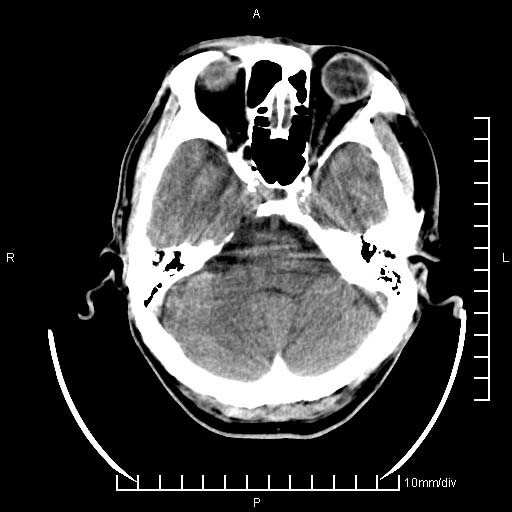

临床以双下肢浮肿,疼痛收治,无明显神经系统症状,既往无梗塞,出血病史。左颞叶见低密度灶,考虑什么?

考虑左侧颞叶脑软化灶。

无强化 无占位 软化灶吧

无强化、 无占位、局部脑沟增宽, 软化灶吧。